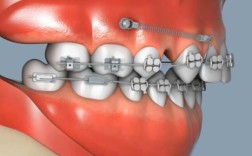

传统正畸治疗中,支抗的控制是难点——若支抗不足,可能导致目标牙齿移动时,支抗牙发生不希望的位置改变(如内收前牙时后牙前移,占据拔牙间隙),种植体支抗(orthodontic implant anchorage)的出现,通过将微型种植体(直径1.5-3.0mm)植入牙槽骨,为正畸提供“绝对支抗”,有效解决了这一难题。

种植体支抗的原理是:种植体与周围骨组织形成骨结合(osseointegration),稳定性远大于天然牙,可在正畸过程中几乎不发生移位,从而将矫治力精准传递至目标牙齿,其植入部位灵活,常见于上颌后牙区(如颧牙槽嵴、磨牙后区)、下颌骨体部等,根据治疗需求可选择临时性(治疗结束后取出)或永久性(留作修复使用)种植体。

当橡皮链与种植体支抗结合时,二者优势互补:种植体支抗提供稳定的“固定点”,橡皮链则作为“力的传递媒介”,实现高效、可控的牙齿移动,以下是常见的协同应用场景及操作逻辑:

操作方法:在上下颌后牙区(如第二磨牙远中)植入微型种植体作为支抗,使用橡皮链一端连接种植体头部附件,另一端连接尖牙或前牙托槽的钩状结构,通过橡皮链的回缩力(约50-200g,根据牙齿移动需求调整)持续牵引前牙向远中移动,种植体支抗确保后牙几乎不前移,拔牙间隙被完全用于前牙内收,矫正效率显著提升(传统方法需6-12个月,结合种植体支抗可缩短至3-6个月)。